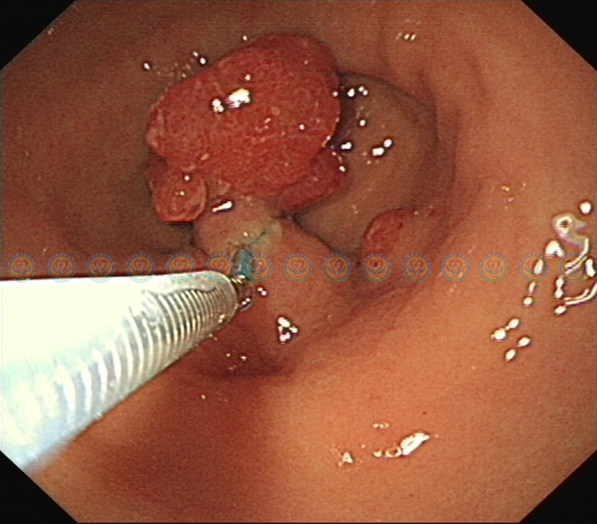

内镜下送入尼龙圈结扎器,结扎肿块蒂部。

结扎后肿块变色、变小,提示结扎有效。